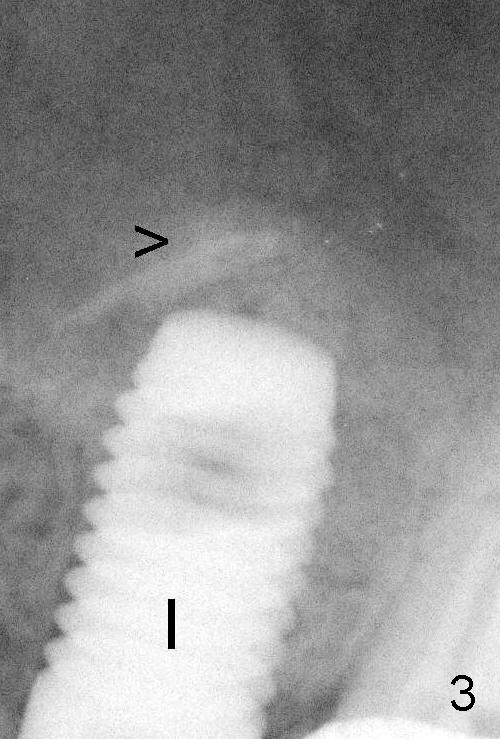

A 5x14 mm cylindrical implant (Fig.3 I) was inserted with elevation of the apparent sinus floor (>, no allograft used in case of sinus infection). Seven months postop, the density of sinus floor increases (Fig.4 <). The implant is stable and processed for crown (Fig.5 C, different view of the lifted sinus floor (<)). While sinus floor density is decreasing, the mesial and distal bone density is increasing 6 months (Fig.6), 1 year 6 months (Fig.7) and 3 year 6 months (Fig.8) post cementa-tion.

It appears necessary to engage an implant into the sinus floor for primary stability for a skinny, probably osteo-porotic female patient. The shape and diameter of the implant are also critical.